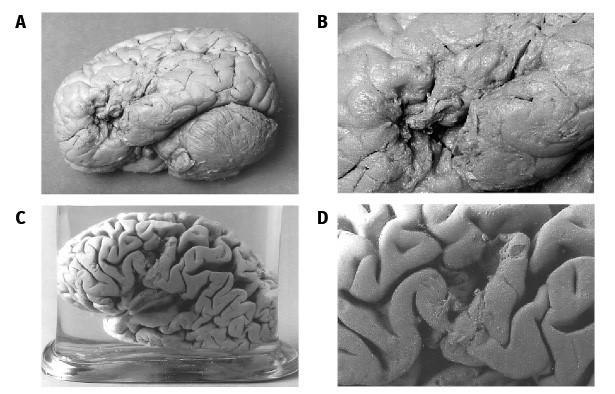

Спустя несколько месяцев после смерти Леборна Полю Брока встретился еще один интересный пациент – 84-летний садовник Лазар Лелон с диагнозом «деменция». При общении с Лелоном врач отметил ярко выраженные проблемы с речью – садовник произносил лишь пять слов: собственное имя, «да», «нет», «всегда», «три» (этим числительным он заменял все остальные). После смерти Лелона хирург исследовал его мозг и обнаружил, что лобные доли были сильно повреждены в том же месте, что и у Луи Леборна. Это укрепило исследователя во мнении, что здесь и находится речевой центр – сегодня он называется зоной Брока (рис. 3).

Рис. 3. Мозг Луи Леборна (А, В) и Лазара Лелона (С, D). Хорошо видны физические повреждения левой лобной доли

Источник: Dronkers et al., 2007

Оба головных мозга были заспиртованы и сейчас хранятся в Париже, в Музее патологической анатомии (Музее Дюпюитрена). Их исследования, проведенные с использованием современных методов, подтвердили и расширили выводы Поля Брока (о том, как изучают мозг в XXI веке, мы поговорим немного позже).